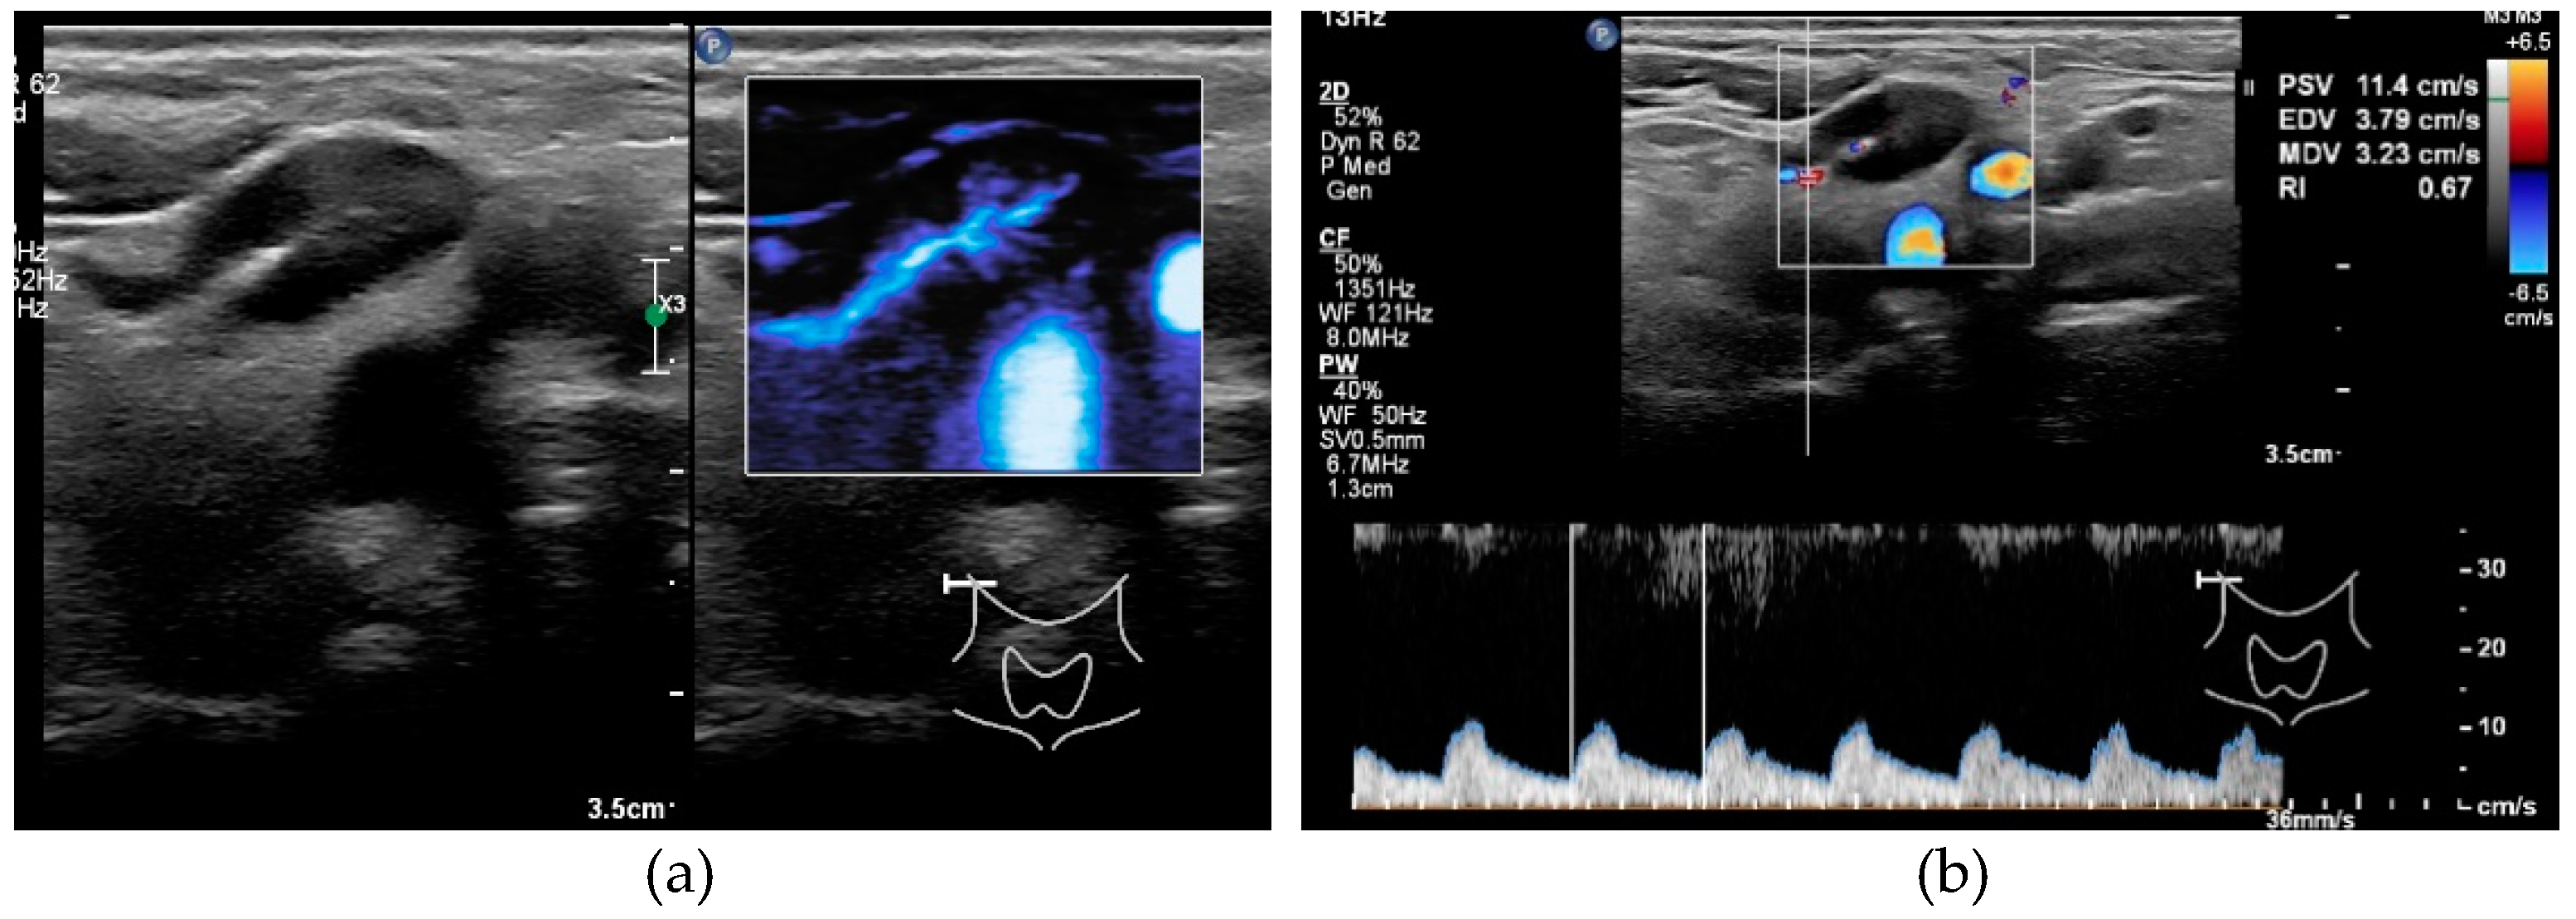

3.1.3. Resistive Index

3.1.4. Peripheral Vascularization